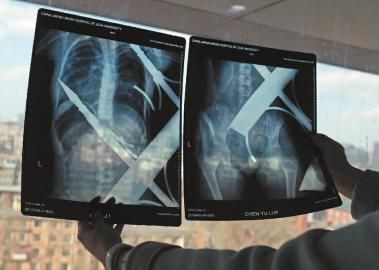

X光片显示一根钢筋将小女孩的右侧肩膀刺穿,另外一根则从后背腰部以上靠近脊椎的地方穿入 新文化记者 白石 摄

在急诊室的病床上,李红旭看到了小雨。“她挂着吊瓶,意识比较清醒。”进一步观察,李红旭一时说不出话来———一根钢筋穿透小雨右侧肩膀,另一根则从后背腰部以上靠近脊椎的地方穿入,从小雨左肩部分穿了出来。两根钢筋由两根角铁连接,距离事发,小雨背着这片铁栅栏已经近7个小时了。